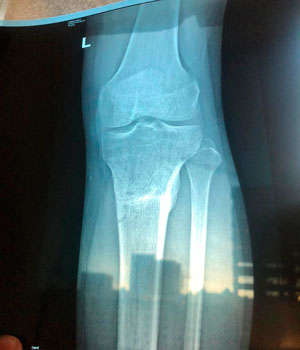

Рентген снимки перед снятием аппаратов.

Вложения

Дата операции -29.04.2019г.

Дата снятия аппаратов -05.09.2019г.

Срок сращения - 128 дней.